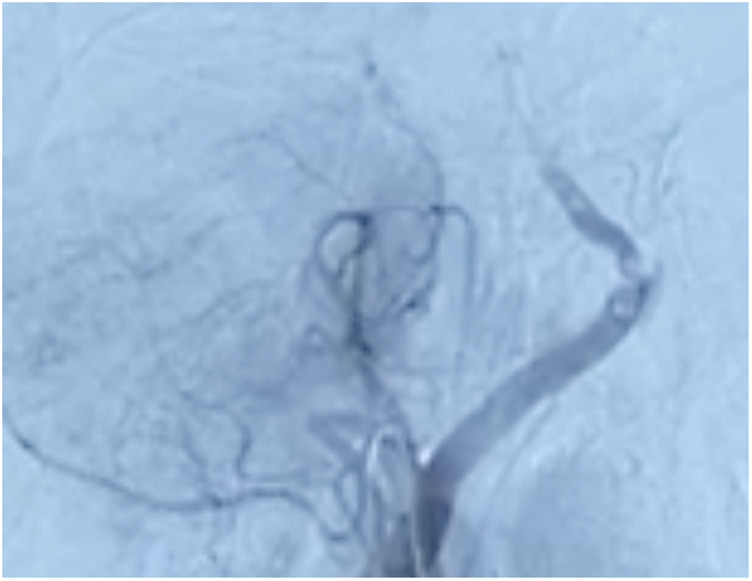

Case presentation: We present the case of a 64-year-old male diagnosed with basilar artery occlusion who underwent a successful mechanical thrombectomy 11 days after symptom onset. Despite complications such as hemorrhagic transformation and herniation, the patient was stabilized and showed functional improvement 3 months post-stroke.